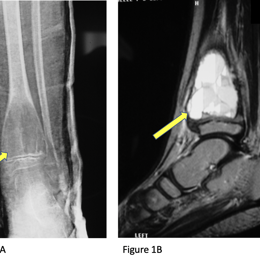

Radiographic imaging is used to help form a diagnosis of ABC. These include X-Ray, MRI, CT and Bone Scans

An example of an ABC X-Ray (Figure 1A) and an MRI (Figure 1B) with fluid fluid levels are shown.